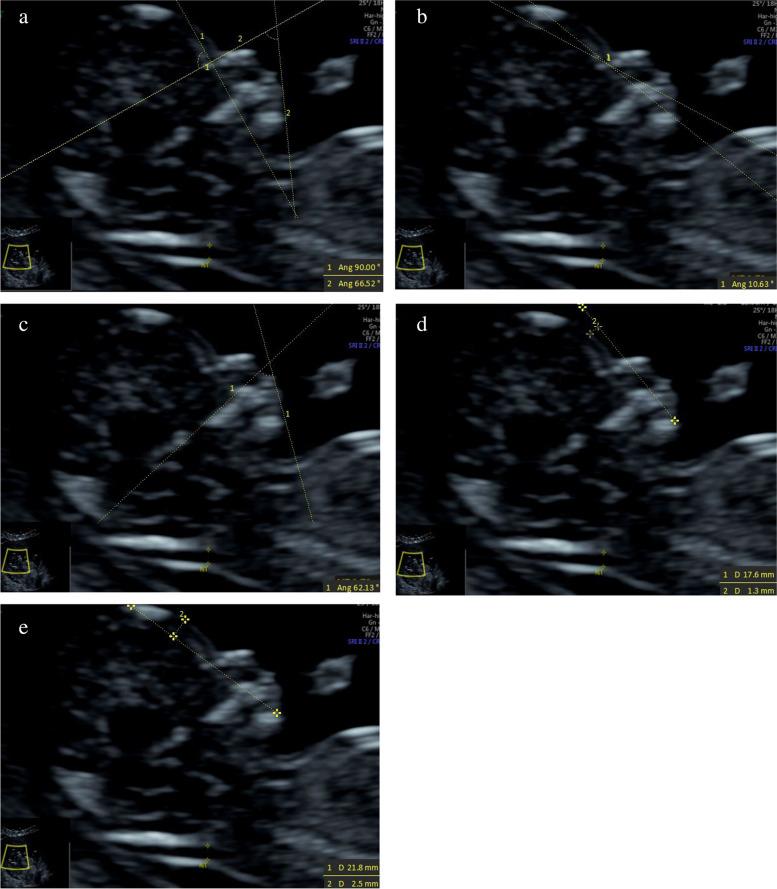

To study the correlations between facial profile markers and crown-lump length (CRL) in a Chinese population, and to evaluate the clinical value of these markers for abnormal fetuses during the first trimester (11 to 13 gestational weeks).  METHODS: The facial profile markers were as followings: inferior facial angle (IFA), maxilla-nasion-mandible (MNM) angle, facial maxillary angle (FMA), frontal space (FS) distance and profile line (PL) distance. These markers were measured in facial mid-sagittal section through ViewPoint 6 software. The diagnostic value of these markers for abnormal fetuses was assessed by receiver operating characteristic (ROC) curves.

According to the first-trimester scanning (FTS) and follow-up, 31 fetuses were enrolled in the abnormal group, including 14 cases of trisomy 21, 7 cases of trisomy 18, 10 cases with cleft lip and palate (CLP), and 1000 normal fetuses were selected. Among the normal fetuses, the IFA, FS distance and PL distance had negative correlations with CRL. The MNM angle and FMA had positive correlations with CRL. The mean IFA values for fetuses with trisomy 21 and trisomy 18 were 74.11° (standard deviation (SD) 7.48) and 69.88° (SD 7.08), respectively, which were significantly smaller than the normal fetuses (p = 0.013; p = 0.003). The mean MNM angle of fetuses with trisomy 18 and CLP were 6.98° (SD 2.61) and 9.41° (SD 2.57), respectively, which were significantly greater than the normal fetuses (p = 0.005; p < 0.001). The mean FMA values of trisomy 18 fetuses were 63.95° (SD 4.77), which was significantly smaller than the normal fetuses (p < 0.001). The mean FS distance of CLP fetuses was -0.22 mm (SD 1.38), which was significantly smaller than the normal fetuses (p < 0.001). The mean PL distance of trisomy 21, trisomy 18 and CLP fetuses were 2.89 mm (SD 0.41), 2.91 mm (SD 0.56) and 2.71 mm (SD 0.37), respectively. The difference with the normal fetuses had no statistical significance (p = 0.56; p = 0.607; p = 0.54).

面部轮廓标志如下:下面部角(IFA)、上颌-鼻根-下颌(MNM)角、面上部角(FMA)、额面间距(FS)和轮廓线(PL)距离。通过 ViewPoint 6 软件在面部正中矢状面测量这些标志。通过受试者工作特征(ROC)曲线评估这些标志对异常胎儿的诊断价值。

根据孕早期扫描(FTS)和随访,31 例胎儿被纳入异常组,包括 14 例 21 三体,7 例 18 三体,10 例唇腭裂(CLP),1000 例正常胎儿。在正常胎儿中,IFA、FS 距离和 PL 距离与 CRL 呈负相关。MNM 角和 FMA 与 CRL 呈正相关。21 三体和 18 三体胎儿的 IFA 平均值分别为 74.11°(标准差(SD)7.48)和 69.88°(SD 7.08),显著小于正常胎儿(p=0.013;p=0.003)。18 三体和 CLP 胎儿的 MNM 角平均值分别为 6.98°(SD 2.61)和 9.41°(SD 2.57),显著大于正常胎儿(p=0.005;p<0.001)。18 三体胎儿的 FMA 平均值为 63.95°(SD 4.77),显著小于正常胎儿(p<0.001)。CLP 胎儿的 FS 距离平均值为-0.22mm(SD 1.38),显著小于正常胎儿(p<0.001)。21 三体、18 三体和 CLP 胎儿的 PL 距离平均值分别为 2.89mm(SD 0.41)、2.91mm(SD 0.56)和 2.71mm(SD 0.37),与正常胎儿相比差异无统计学意义(p=0.56;p=0.607;p=0.54)。